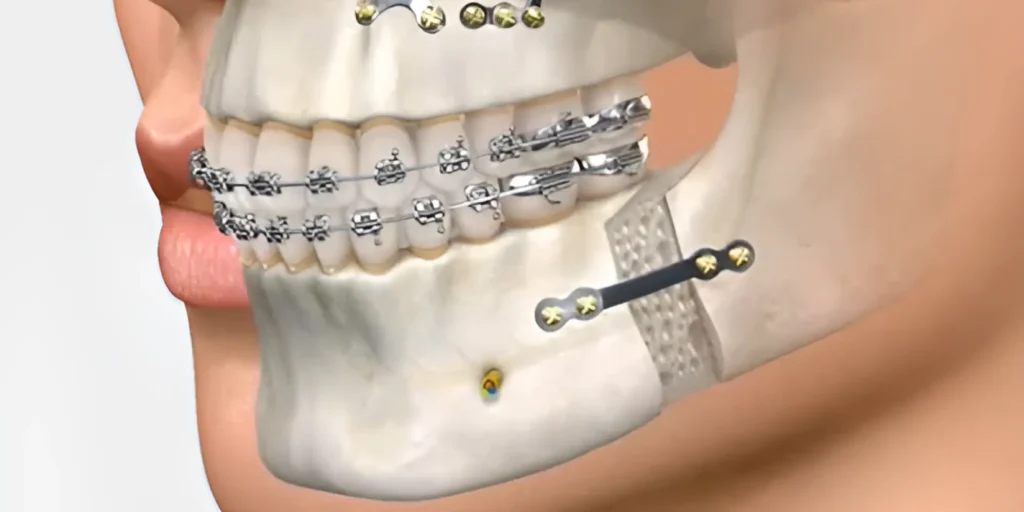

Ortodontia

A ortodontia é a especialidade que corrige a posição dos dentes e dos ossos maxilares, proporcionando um sorriso não apenas mais bonito, mas também mais saudável. O Dr. Ely Nardello oferece tratamentos ortodônticos modernos e eficientes para crianças, adolescentes e adultos, visando o alinhamento dental ideal, a melhora da mastigação e da fala. Invista na sua autoestima e saúde bucal com a ortodontia especializada.

CTBMF

A Cirurgia e Traumatologia Bucomaxilofacial (CTBMF) é a especialidade que trata de doenças e traumas que afetam a boca, face e pescoço. O Dr. Ely Nardello possui expertise para realizar diversos procedimentos cirúrgicos, desde extrações de dentes inclusos (como o siso) até cirurgias mais complexas, visando restaurar a função e a estética da região bucomaxilofacial com segurança e precisão.